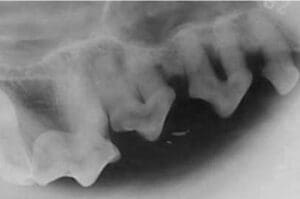

General anesthesia is needed for complete evaluation. During the examination, each area around the tooth is explored with a periodontal probe. The periodontal probe measures the depth of pockets and tissue loss around the teeth. Dental x-rays also assess for any periodontal tissue loss around the teeth. The classification system used here uses a system of Stage 1 through Stage 4.

Significant gingivitis and bone involvement is present. Teeth are becoming mobile as moderate calculus, gum recession, and gingival pockets  are also noted. Irreversible tooth damage may be present and these patients often require advanced periodontal therapy or oral surgery.

Stage 4 – SEVERE

Teeth have advanced breakdown of support tissues with severe pocket depth.  Signs include severe calculus accumulation, dead tissue with blood and pus, severe halitosis, significant bone loss, and mobility of teeth. Patients require tooth extractions and oral surgery.